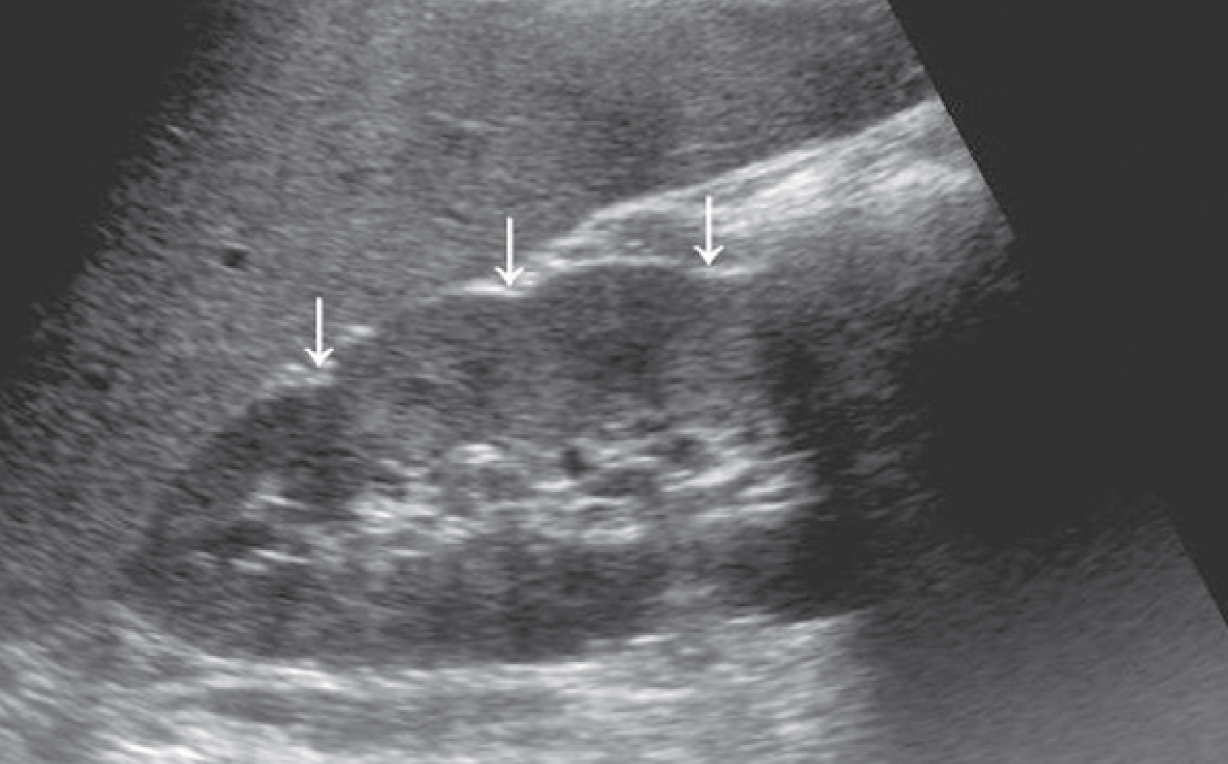

2-Kidney hump

تسمى أيضا Dromedary hump وهي مثل البروز في شكل parenchyma الكلية كسنام الجمل. سماكتها يجب أن تتناسق مع بقية parenchyma المحيطة بدون بروز. هي شائعة تحديدا في الكلية اليسرى وذلك لأن التغير يحدث في مرحلة تطور الجنين وضغط الطحال على الكلية.

في هذه الحالات يجب التأكد من السماكة (متناسقة) و echogenicity (غير مختلفة) و colour Doppler (طبيعية).